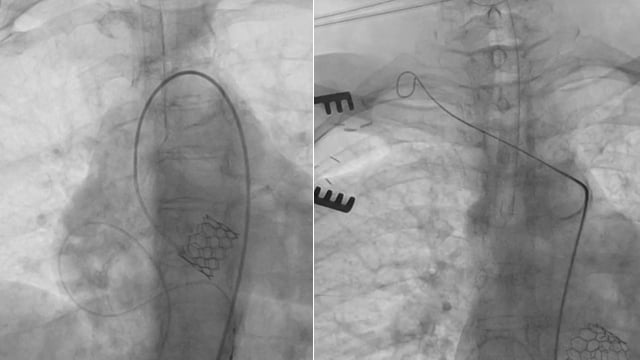

Emergency transcatheter valve interventions: alternative therapy or bridge to surgery?

16 Nov 2025 – From PCR London Valves 2025

This session offers a compelling case-based exploration of emergency transcatheter valve interventions, demonstrating their potential as life-saving alternatives or bridges to surgery in high-risk patients. Through detailed clinical scenarios including cardiogenic shock, acute papillary muscle rupture, and severe aortic regurgitation from infective endocarditis, participants gain practical...